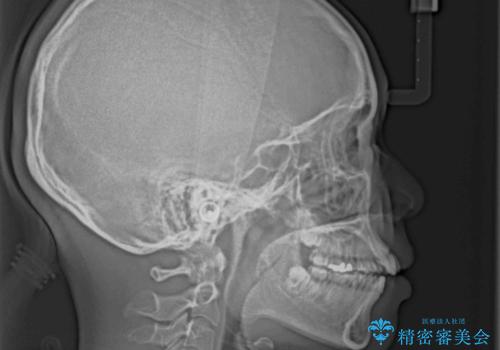

- 下顎小臼歯が欠損しており、さらに上顎が全体的に突出していることを気にして来院された患者様です。

下顎は片方の小臼歯が欠損していたため、正中がずれた上に、上下前歯が接触していない状態でした。

上顎左右の小臼歯2本および下顎小臼歯を1本抜歯し、補助装置を用いて上顎大臼歯が前方に移動しないように固定した上で、ワイヤー装置にて矯正治療を行うこととしました。